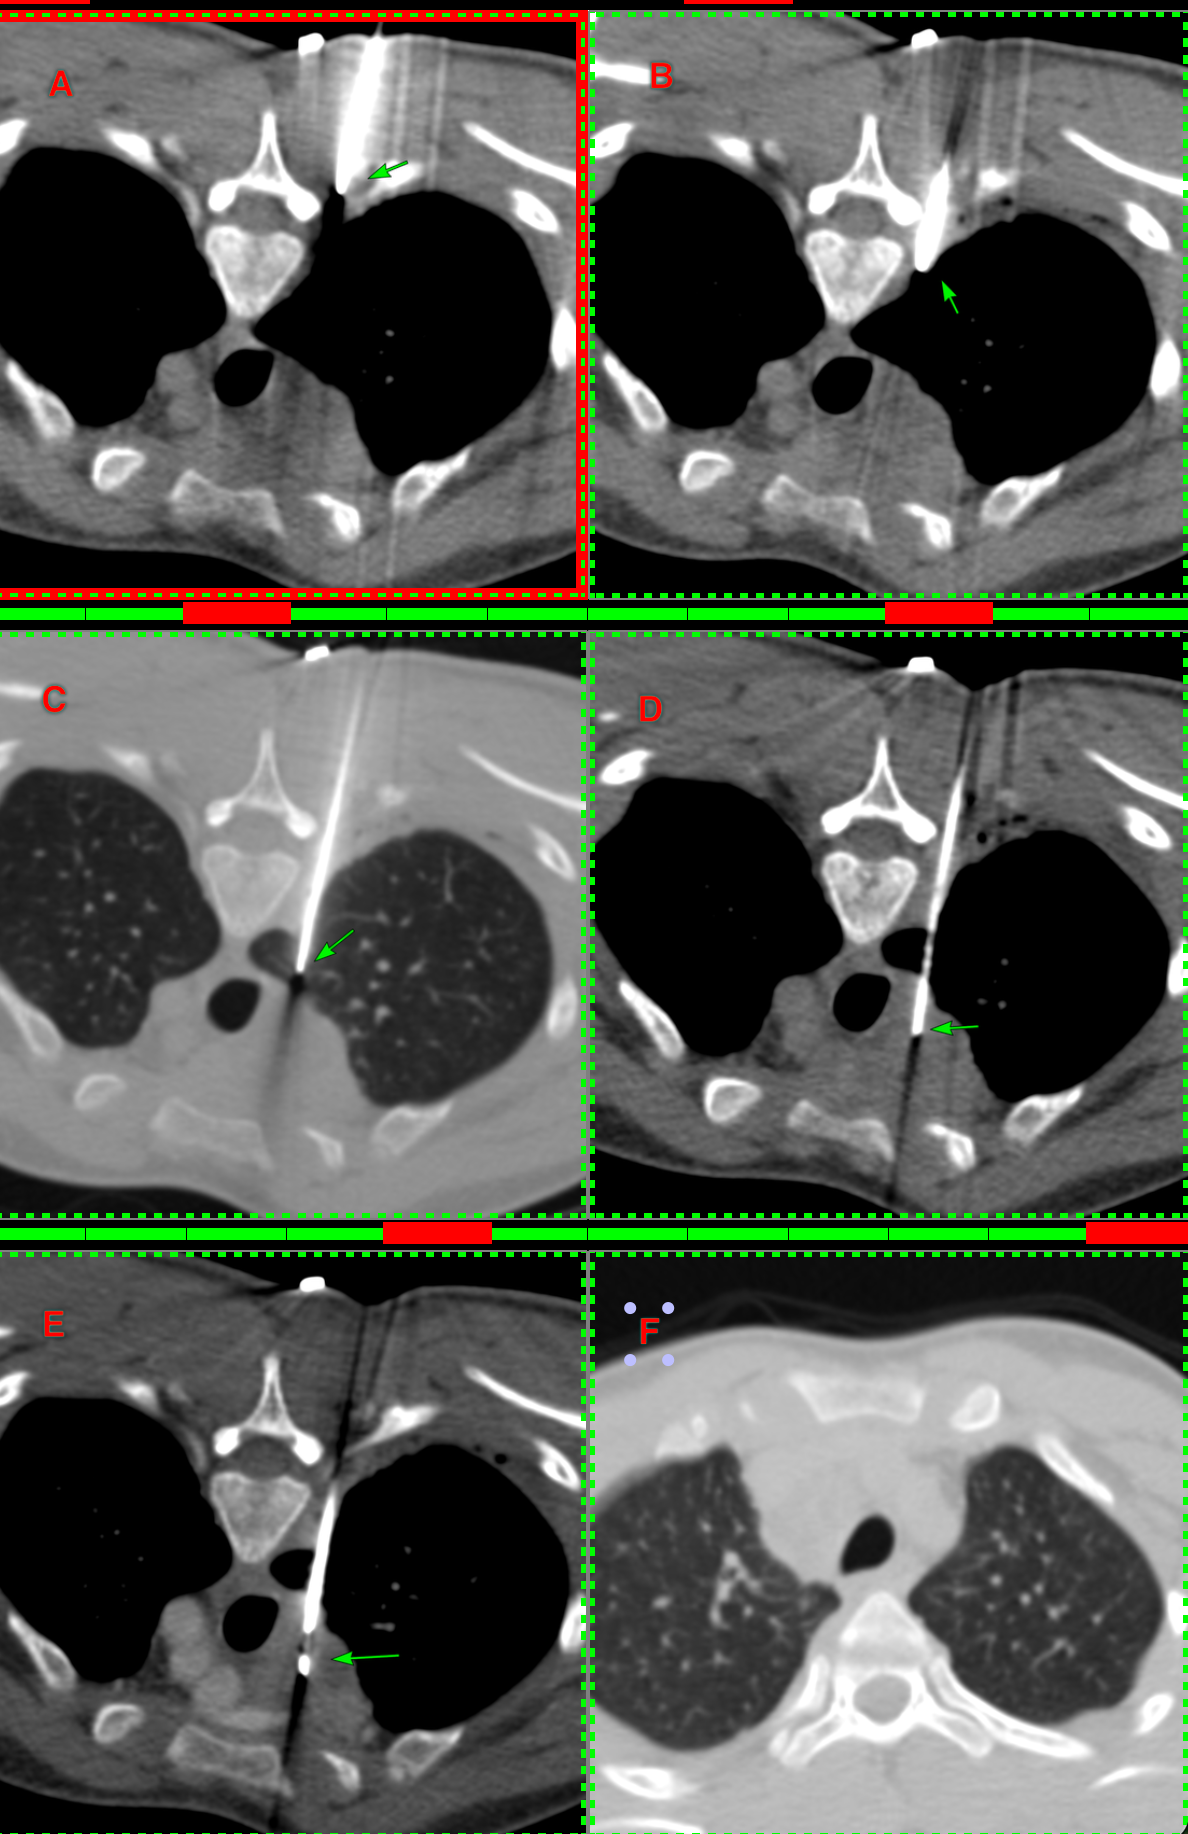

The next figure shows the procedure. An 18G BARD needle was introduced into the clear space next to the foramen (A) and 10 cc of lignocaine was injected just over the pleura (B). The needle was then passed through a sliver of the lung (C) and then through it into the node (D). 5 cc of pus was aspirated and then intravenous contrast was given before deploying the gun - a hub was used to deploy only 10 mm so as not to overshoot (E). The rapid rollover (F) shows no pneumothorax or hemorrhage. It took 11 minutes.

In the young, it is rare to get a pneumothorax when going through otherwise normal lung and unless you go through a big vessel, hemorrhage is also unlikely. The only thing to take care of is not to overshoot into the mediastinal vessels.

The diagnosis was GeneXpert and histopath positive tuberculosis.